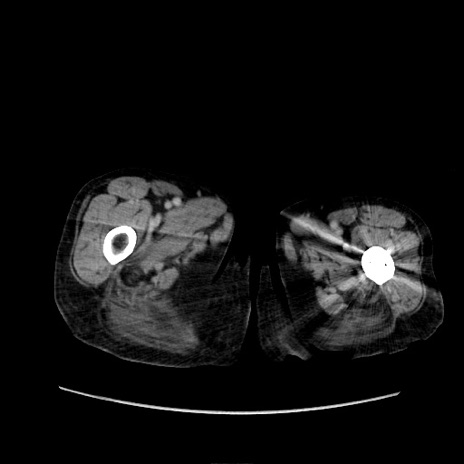

冠状断像